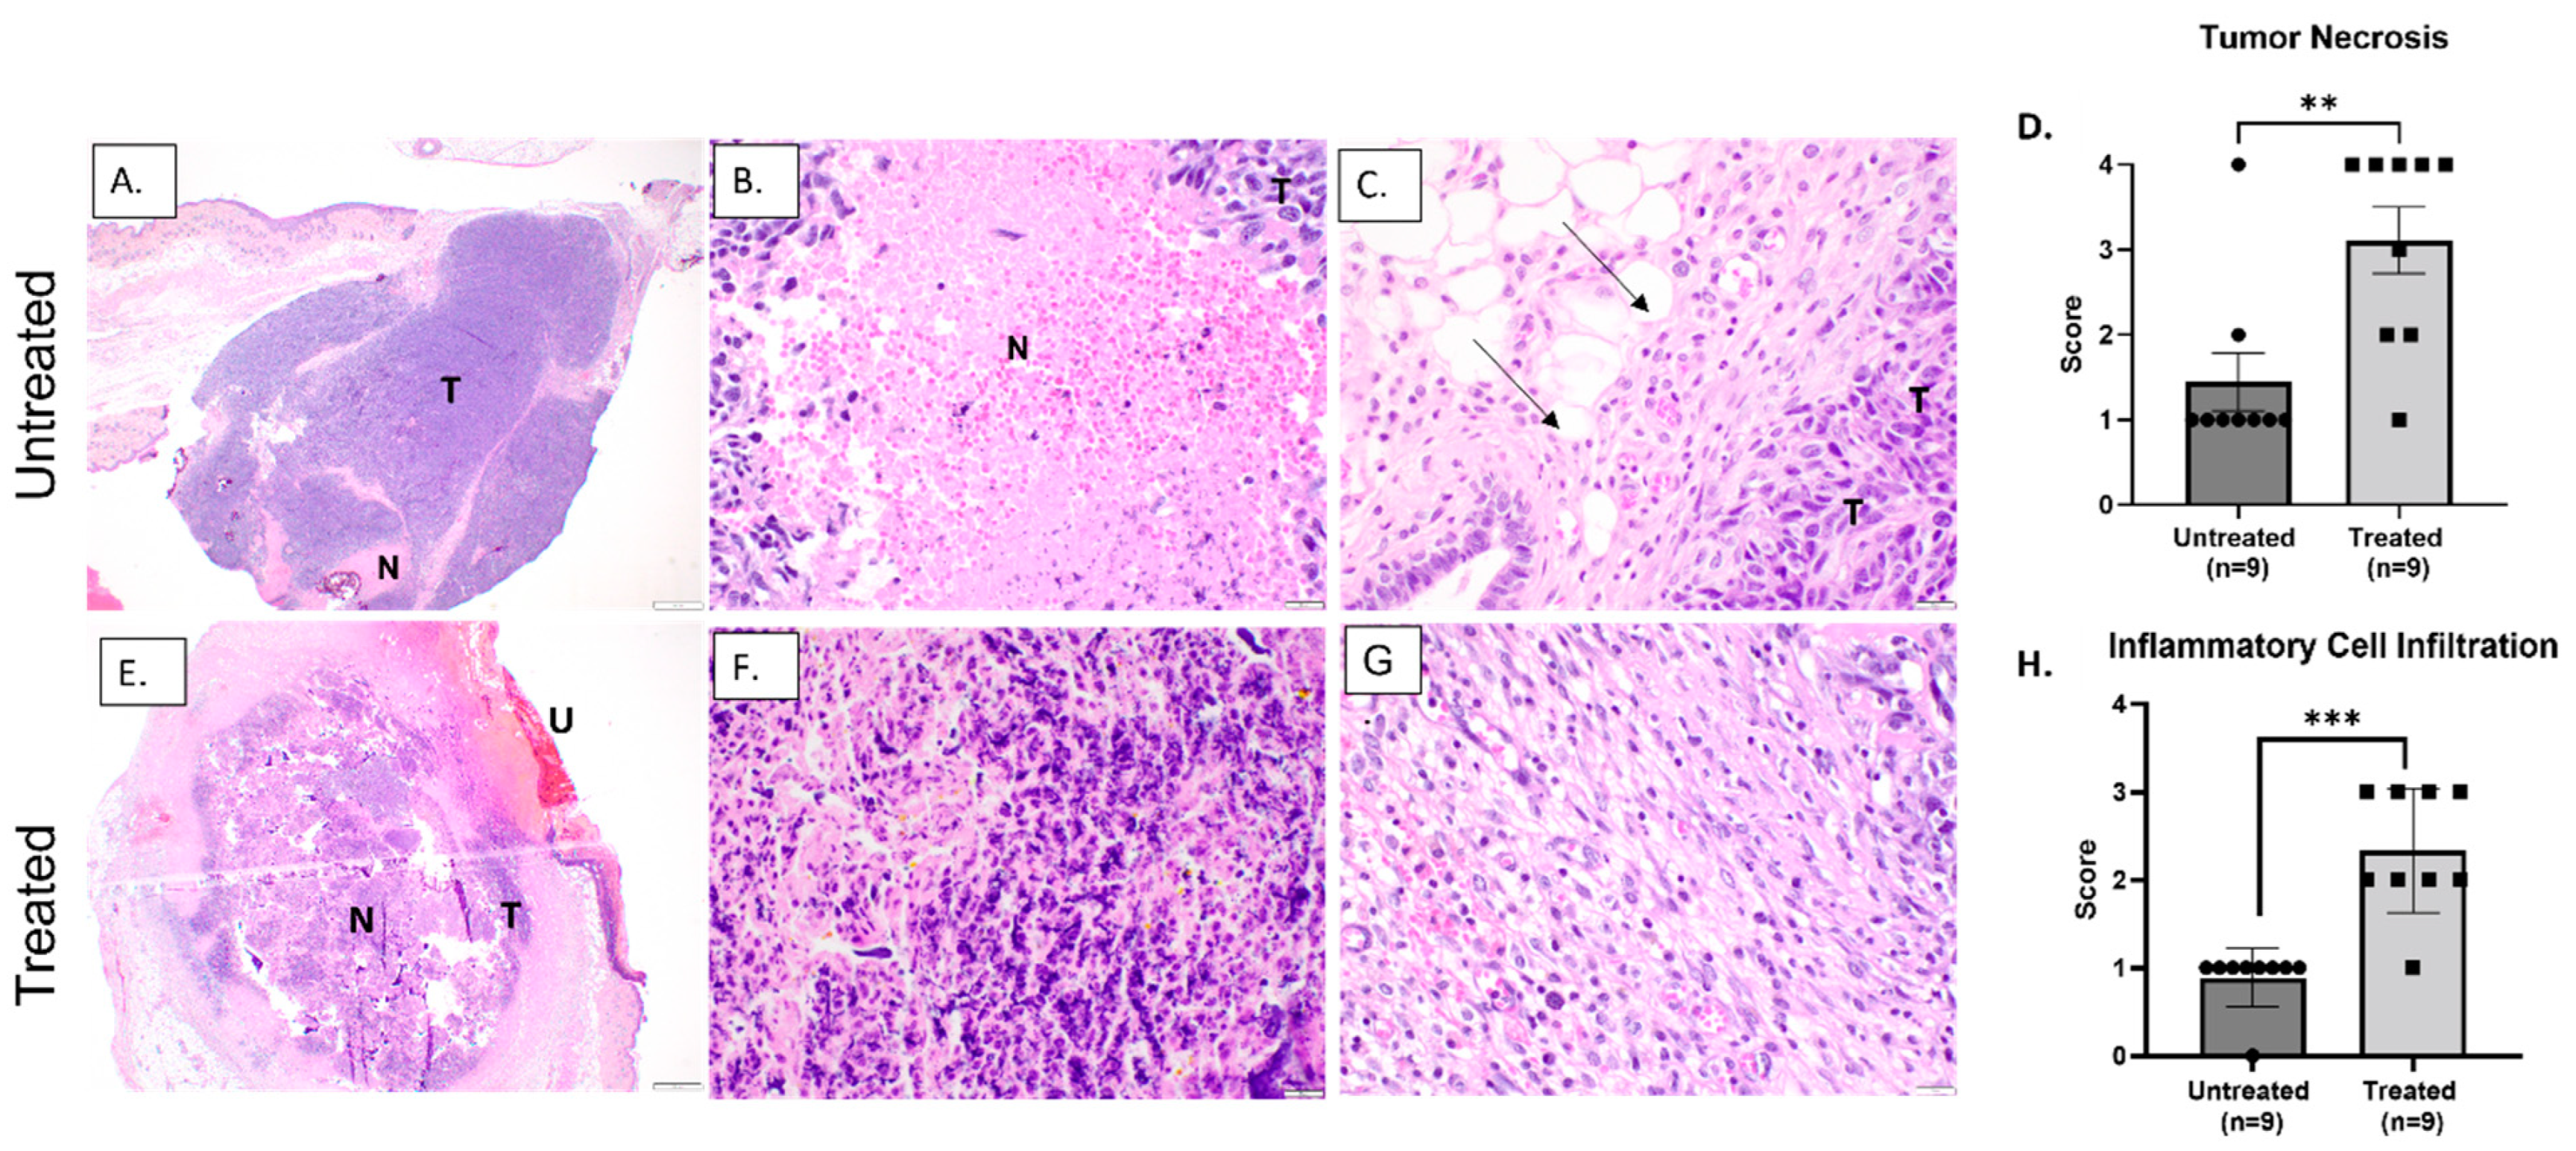

3.2. Histotripsy Ablation Resulted in Effective Tumor Tissue Destruction, Necrosis, and Immune Cell Infiltration

3.3. Histotripsy Ablation Induces Immune Activation within the TME